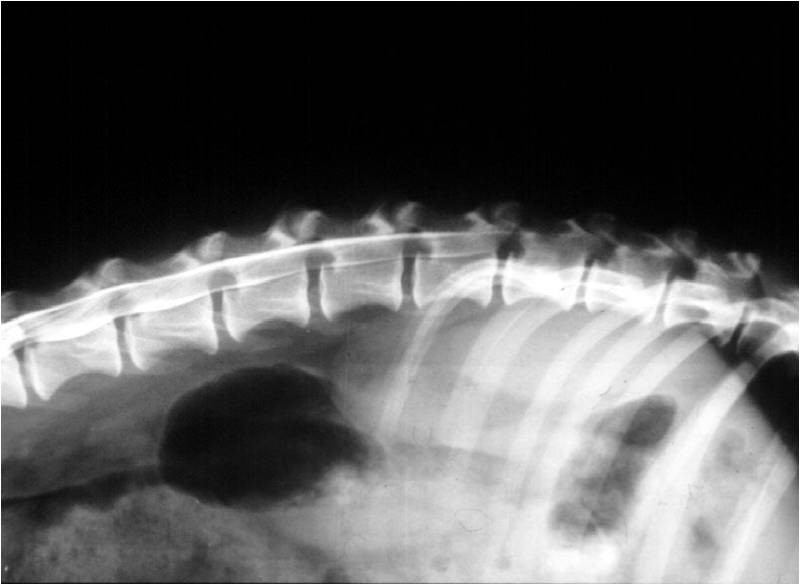

Nyaki myelogram